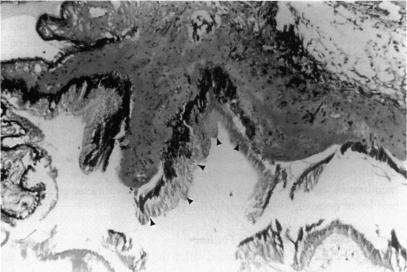

RESULTS

ANIMAL MODEL: Histopathologic examination of rabbit eyes treated with endocyclophotocoagulation demonstrated acute changes of ciliary process destruction, proteinaceous exudate, stromal edema, nuclear pyknosis, and pigment dispersion. Vascular congestion was seen with some hemorrhage. Later, replacement by fibrous or fibrovascular scar developed with loss of the pigmented and nonpigmented ciliary epithelia, absence of ciliary architectural elements, and pigment rounding and clumping. Human Eyes: Histopathologic examination of enucleated human eyes revealed total ablation of the ciliary processes with fibrosis and pigment clumping in areas of treatment. Abrupt transitions between treated and untreated regions could be identified. In some areas fibrocellular membrane proliferation was found extending over the scars that replaced the ciliary processes. Clinical series: Seventy-three patients were identified ranging in age from 2 to 85 years (mean, 57.7), with follow-up of 6 to 130 months (mean, 28.6). Mean number of previous operations was 3.5; mean number of previous glaucoma operations was 1.3. Preoperative mean IOP was 38 mmHg (range, 19 to 75), postoperative mean IOP was 16 mmHg (range, 1 to 50). At 6 months, 58 of 72 eyes (81%) with available IOP data had IOP greater than 5 mmHg and less than 22. At 12 months 48 of 55 (87.3%) were successfully controlled by these criteria, and at last follow-up 50 of 73 (68%). Fifty-six of 73 eyes (77%) were considered clinically stable at the last follow-up in terms of visual acuity, anatomic integrity, and IOP < or = 23 off all glaucoma medications. Visual acuity was stable or improved in 53 of 73 eyes (73%). Complications developed in 9 eyes (12%), including IOP < or = 6 mmHg in 6 eyes (8.2%), peripheral choroidal effusion in 4 (5.5%), fibrinous anterior chamber reaction in 3 (4.1%), phthisis in 2 (2.7%), and choroidal hemorrhage in 1. Thirty-five eyes had penetrating keratoplasty performed before or at the same time as endolaser (an average of 2.14 grafts each), Graft rejection occurred in 4 eyes (11%), and long-term failure of grafts occurred in 11 of 35 (31%). In 31 eyes, additional surgical procedures were performed at the time of endocyclophotocoagulation.

动物模型:经睫状体光凝术治疗的兔眼组织病理学检查显示睫状体破坏、蛋白质渗出、基质水肿、核固缩和色素弥散的急性变化。可见血管充血伴一些出血。之后,出现纤维或纤维血管瘢痕替代,色素性和非色素性睫状体上皮消失,睫状体结构成分缺失,色素聚集。人眼:摘除的人眼组织病理学检查显示睫状体完全消融,治疗区域有纤维化和色素聚集。可识别出治疗区域与未治疗区域之间的突然转变。在一些区域发现纤维细胞膜增生延伸至替代睫状体的瘢痕上。临床系列:共识别出73例患者,年龄2至85岁(平均57.7岁),随访6至130个月(平均28.6个月)。既往手术平均次数为3.5次;既往青光眼手术平均次数为1.3次。术前平均眼压为38 mmHg(范围19至75 mmHg),术后平均眼压为16 mmHg(范围1至50 mmHg)。在6个月时,72只可获得眼压数据的眼中,58只(81%)眼压高于5 mmHg且低于22 mmHg。在12个月时,55只眼中的48只(87.3%)按此标准眼压得到成功控制,在最后一次随访时,73只眼中的50只(68%)眼压得到控制。在最后一次随访时,73只眼中的56只(77%)在视力、解剖结构完整性及停用所有青光眼药物后眼压≤23 mmHg方面被认为临床稳定。73只眼中的53只(73%)视力稳定或提高。9只眼(12%)出现并发症,包括6只眼(8.2%)眼压≤6 mmHg,4只眼(5.5%)周边脉络膜积液,3只眼(4.1%)纤维素性前房反应,2只眼(2.7%)眼球痨,1只眼脉络膜出血。35只眼在激光睫状体光凝术前或同时进行了穿透性角膜移植术(平均每只眼2.14次移植),4只眼(11%)发生移植排斥,35只眼中11只(31%)移植长期失败。31只眼在激光睫状体光凝术时进行了额外的手术操作。